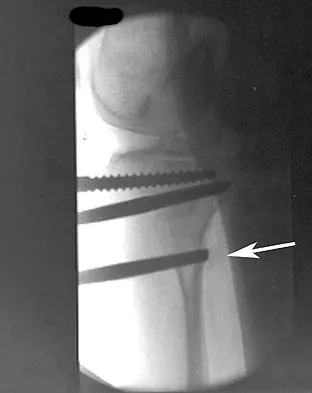

A 58-year-old woman is seen in the emergency department after falling at home. History reveals that she underwent right total knee arthroplasty 2 years ago. Radiographs are shown in Figures 56a and 56b. What is the most appropriate treatment?

Options:

- Closed reduction and casting

- Bed rest and skeletal traction

- Open reduction and internal fixation

- Retrograde intramedullary nailing

- Revision of the femoral component with a stemmed component

Correct Answer: Open reduction and internal fixation

Explanation:

The radiographs show an oblique periprosthetic distal femoral fracture. Of the options listed, open reduction and internal fixation is the most appropriate surgical option because a well-fixed, posterior stabilized closed box femoral component is present. Nonsurgical methods are not favored because of the highly displaced, unstable fracture pattern and prolonged immobility. Revision with a stemmed component is an option but would sacrifice more bone stock in this younger patient. Moran MC, Brick GW, Sledge CB, et al: Supracondylar femoral fracture following total knee arthroplasty. Clin Orthop 1996;324:196-209. Raab GE, Davis CM III: Early healing with locked condylar plating of periprosthetic fractures around the knee. J Arthroplasty 2005;20:984-989.